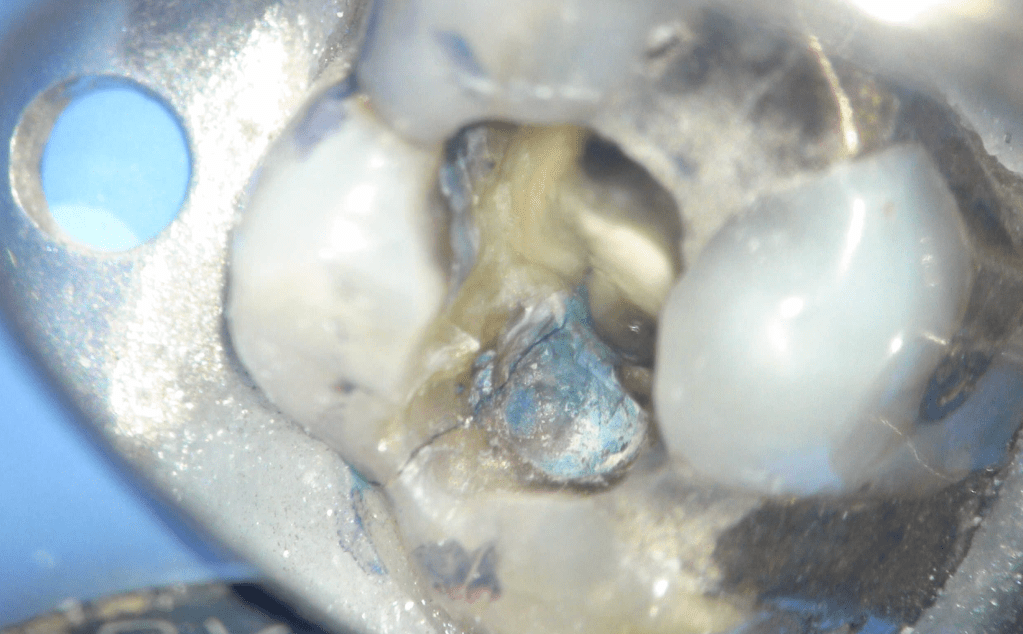

Fisura, remoción amalgama para explorar